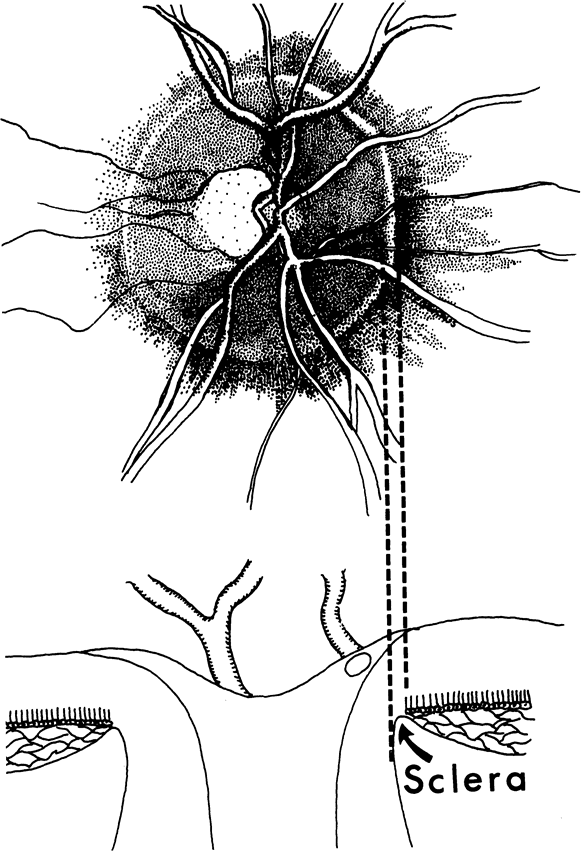

When bundles of nerve fibers drop out, their absence can be noted in the retinal sheen produced by the retinal nerve fiber layer.4,8–10,85 Such defects are easiest to see in the thickest portions of the nerve fiber layer, namely, close to the disc and especially in the arcuate bundles approaching the poles of the disc.5,6 The loss of nerve fibers can be recognized ophthalmoscopically but, as shown in Figure 41, is demonstrated most beautifully in wide-angle fundus photographs taken with blue or green filters.10,154 It is difficult to see if the background is lightly pigmented or if imperfect media produce an imperfect view of the fundus. Some observers are more skilled than others in recognizing nerve-fiber layer disease.

Fig. 41. Retinal nerve fiber layer in glaucoma. A curved wedge (between the broad arrows) represents the loss of nerve fiber bundles corresponding to a sector of the disc marked by a splinter hemorrhage (small curved arrow). (Airaksinen PJ. Mustonen E. Alanko HI: Optic disc hemorrhages precede retinal nerve fiber layer defects in ocular hypertension. Acta Ophthalmol 59:627, 1981.)